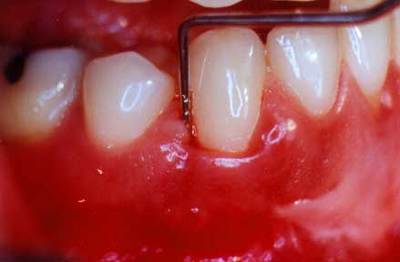

Фиброзный тип

Во время такого вида заболевания происходит поражение всего нескольких зубов. Сильного отёка не наблюдается, припухлость может быть только незначительной, у основания десны.

Фото 4. При поражении полости рта фиброзным гингивитом изменение тканей может происходить как с внешней, так и с внутренней стороны.

Цвет десны остаётся неизменным, в редких случаях меняется на серый. Отсутствуют болезненные ощущения, кровоточивость, но происходит увеличение объёма десны.